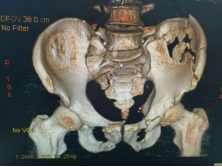

5.复杂骨盆骨折